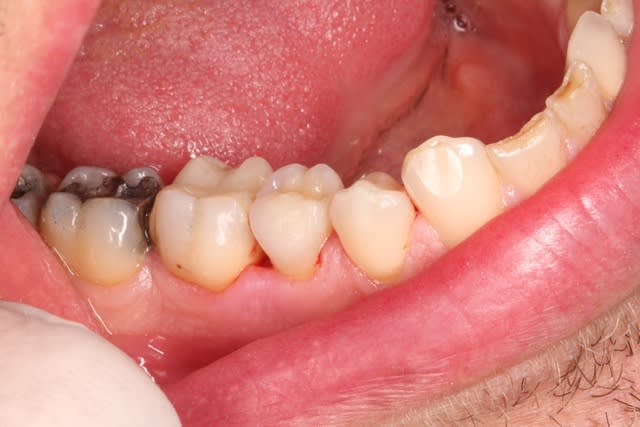

ça marche aussi sur dents vivantes ! patient venu pour me voir un inlay sur 45 qui s'est décollé une dizaine de fois , cas tout frais de ce matin

17/10/2014 à 19h48